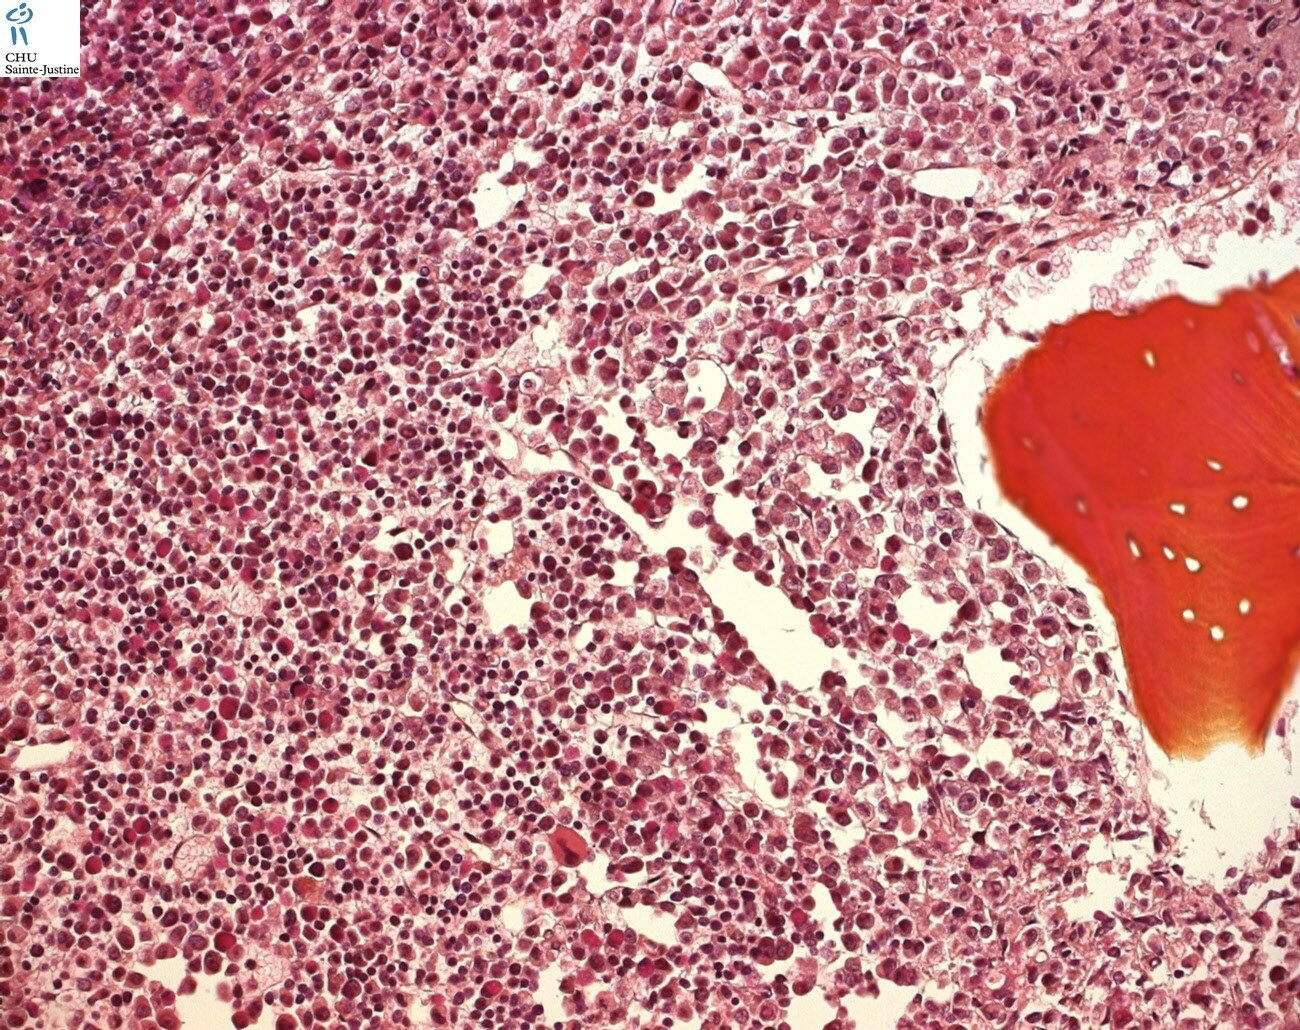

Morphology